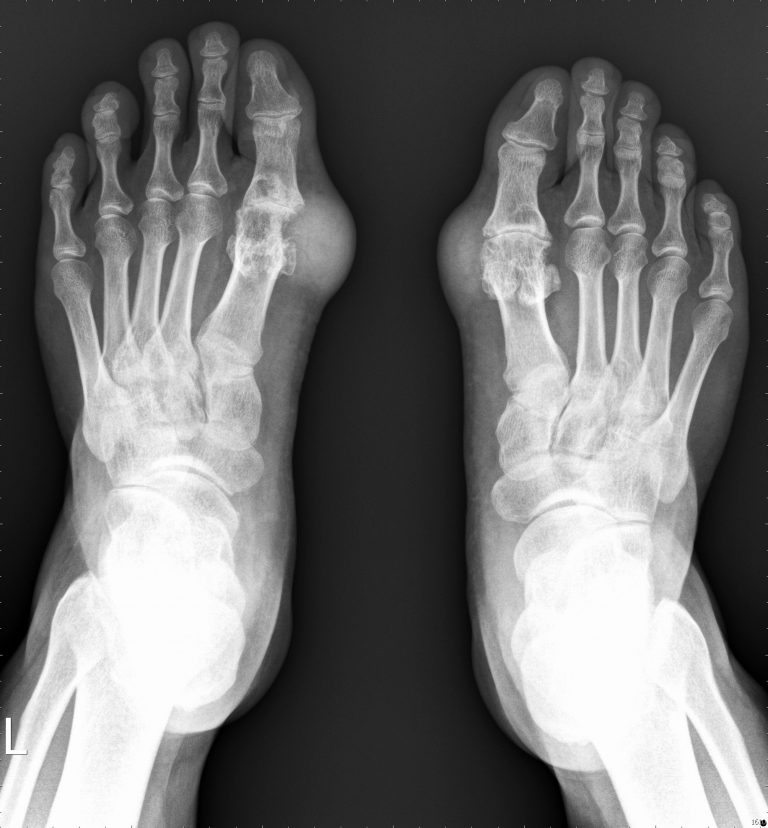

臨床上,關節痛風的症狀相當明顯,疼痛、腫脹、發紅、發熱、關節僵直,但仍須小心與化膿性關節炎或是特定部位的蜂窩性組織炎做鑑別診斷。持續的關節痛風不止會造成反覆的疼痛,尿酸鹽的結晶體也會慢慢堆積在關節或是軟組織(如圖一),形成白色的痛風石,漸而侵蝕及破壞關節組織,造成關節炎或是骨頭缺損(如圖二)。

(圖一)

(圖二)